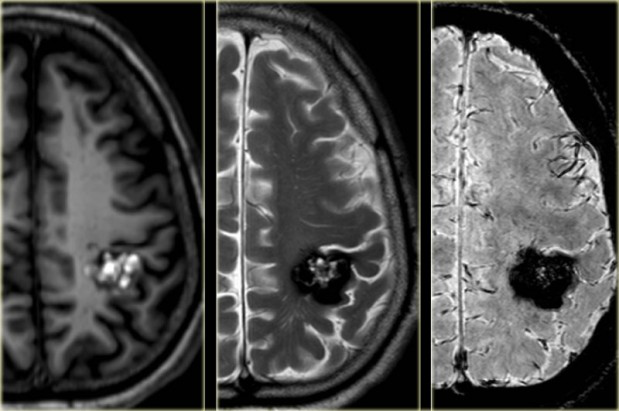

什么是脑血管瘤?事实上,这是诱发出血性脑卒中的常见原因之一,脑血管瘤就像隐藏在人体内的一颗炸弹,察觉不出症状,却随时可能破裂危及生命。

危险的脑血管瘤疾病如脑海绵状血管瘤、脑动脉瘤、脑动静脉畸形等治疗方式各不一样,比如脑海绵状血管瘤一般以全切为主,全切后一般可获治愈。而脑动脉瘤通常可通过开颅夹闭手术或血管栓塞术来治疗,及时治疗一般预后较好。